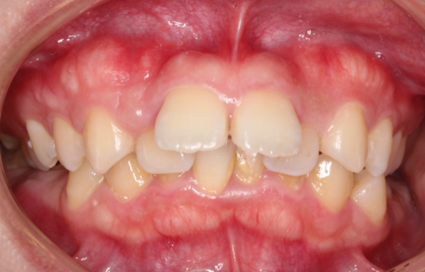

歯がデコボコに並んだ歯並びのことを「叢生(そうせい)」と言います。「乱ぐい歯」という名前でも知られています。叢生の歯並びの中で、よく知られているのが、上顎の犬歯が前方に突出している「八重歯」です。八重歯は可愛らしいイメージに捉えられることもありますが、歯並びとしては良くない、デコボコ歯並びの一種です。

叢生の原因は、顎の骨が小さく、歯が並ぶための十分なスペースが確保できないことが挙げられます。

叢生による問題は、見た目だけではありません。次のような様々な「リスク」があります。

歯並びが乱れていると、ブラッシングが難しい部分があり、汚れや歯垢が残りやすくなります。これにより、虫歯や歯周病のリスクが高まります。